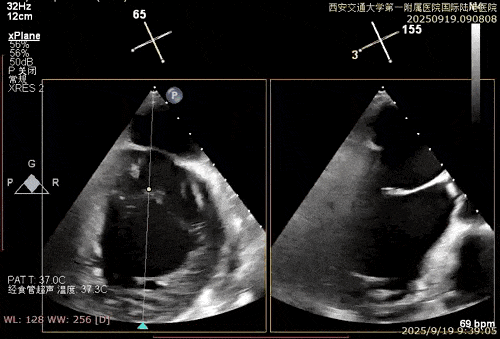

患者男性,69岁,术前TEE评估为FMR患者,因左室功能异常引发二尖瓣重度反流;后叶拴系,反流来源于整个2区,主要集中在2偏1、2偏3。患者瓣口面积约6.2cm²。房间隔可穿刺高度4.5cm。反流束宽度约19mm。AP径36.5mm。

术中在超声引导下完成房间隔穿刺,将第一枚XTR在左房内完成终定位,2偏3区完成植入,夹合效果良好,即刻超声显示轻微反流,完成夹子释放,手术效果良好,手术圆满结束,患者术后6小时即实现床旁活动。

经导管二尖瓣钳夹术作为近年来国际公认的微创治疗新技术,通过经血管介入路径,在食道超声与DSA影像引导下,利用特制钳夹将病变的二尖瓣叶边缘夹合,减少瓣口反流,从而改善心脏功能。